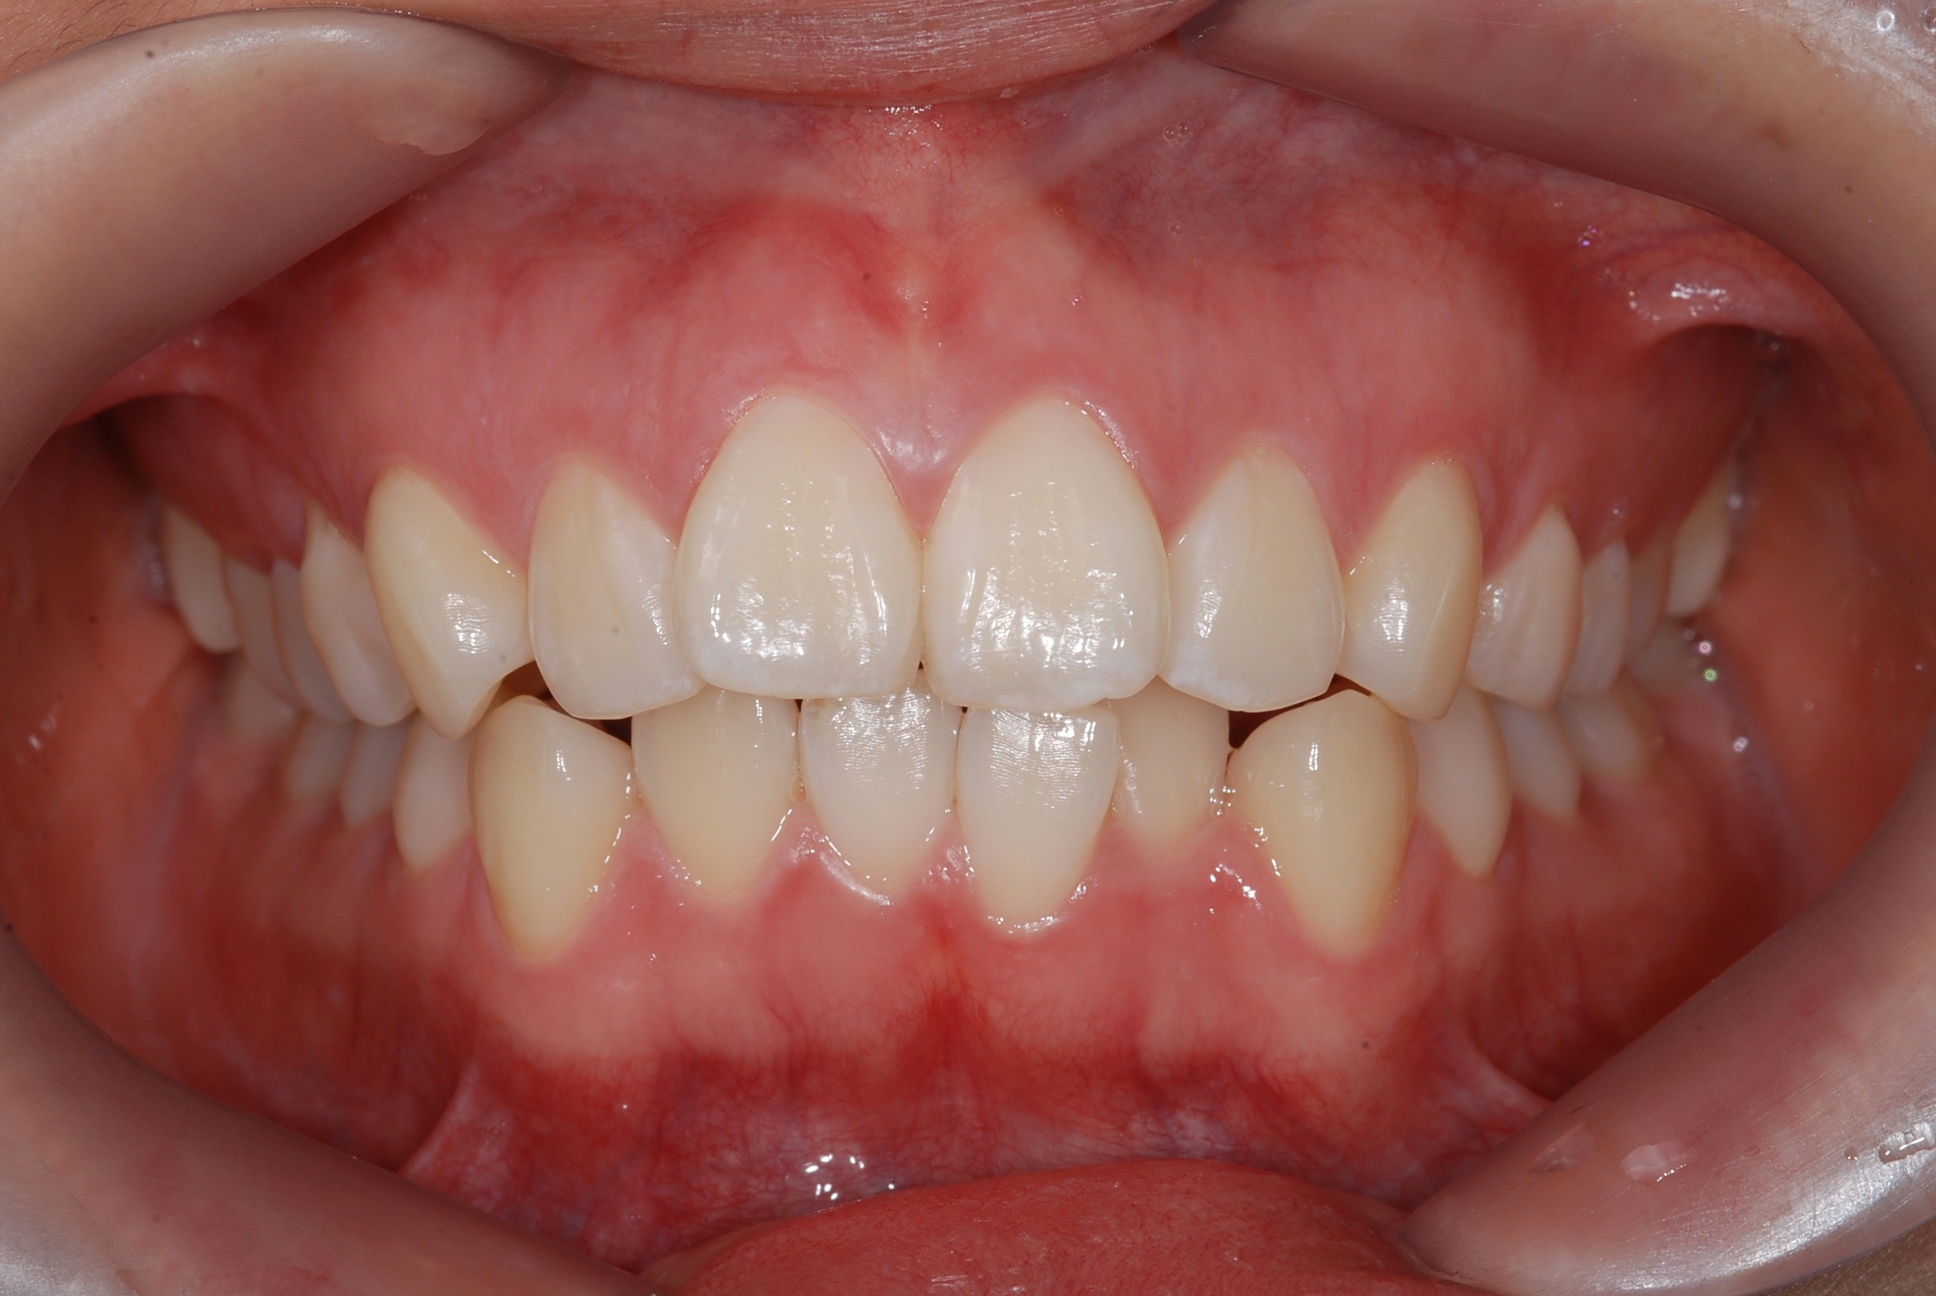

치료 전 사진입니다.